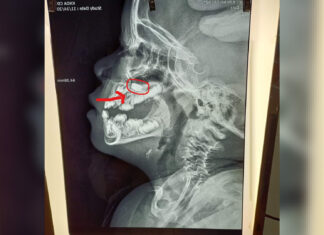

Lâm Đồng: Gây mê để lấy viên pin điện tử trong mũi bệnh nhi...

Do trẻ đau và hoảng sợ nên việc thăm khám và nội soi gặp nhiều khó khăn, do đó, các bác sỹ Bệnh viên II Lâm Đồng phải chuyển phòng mổ gây mê để...